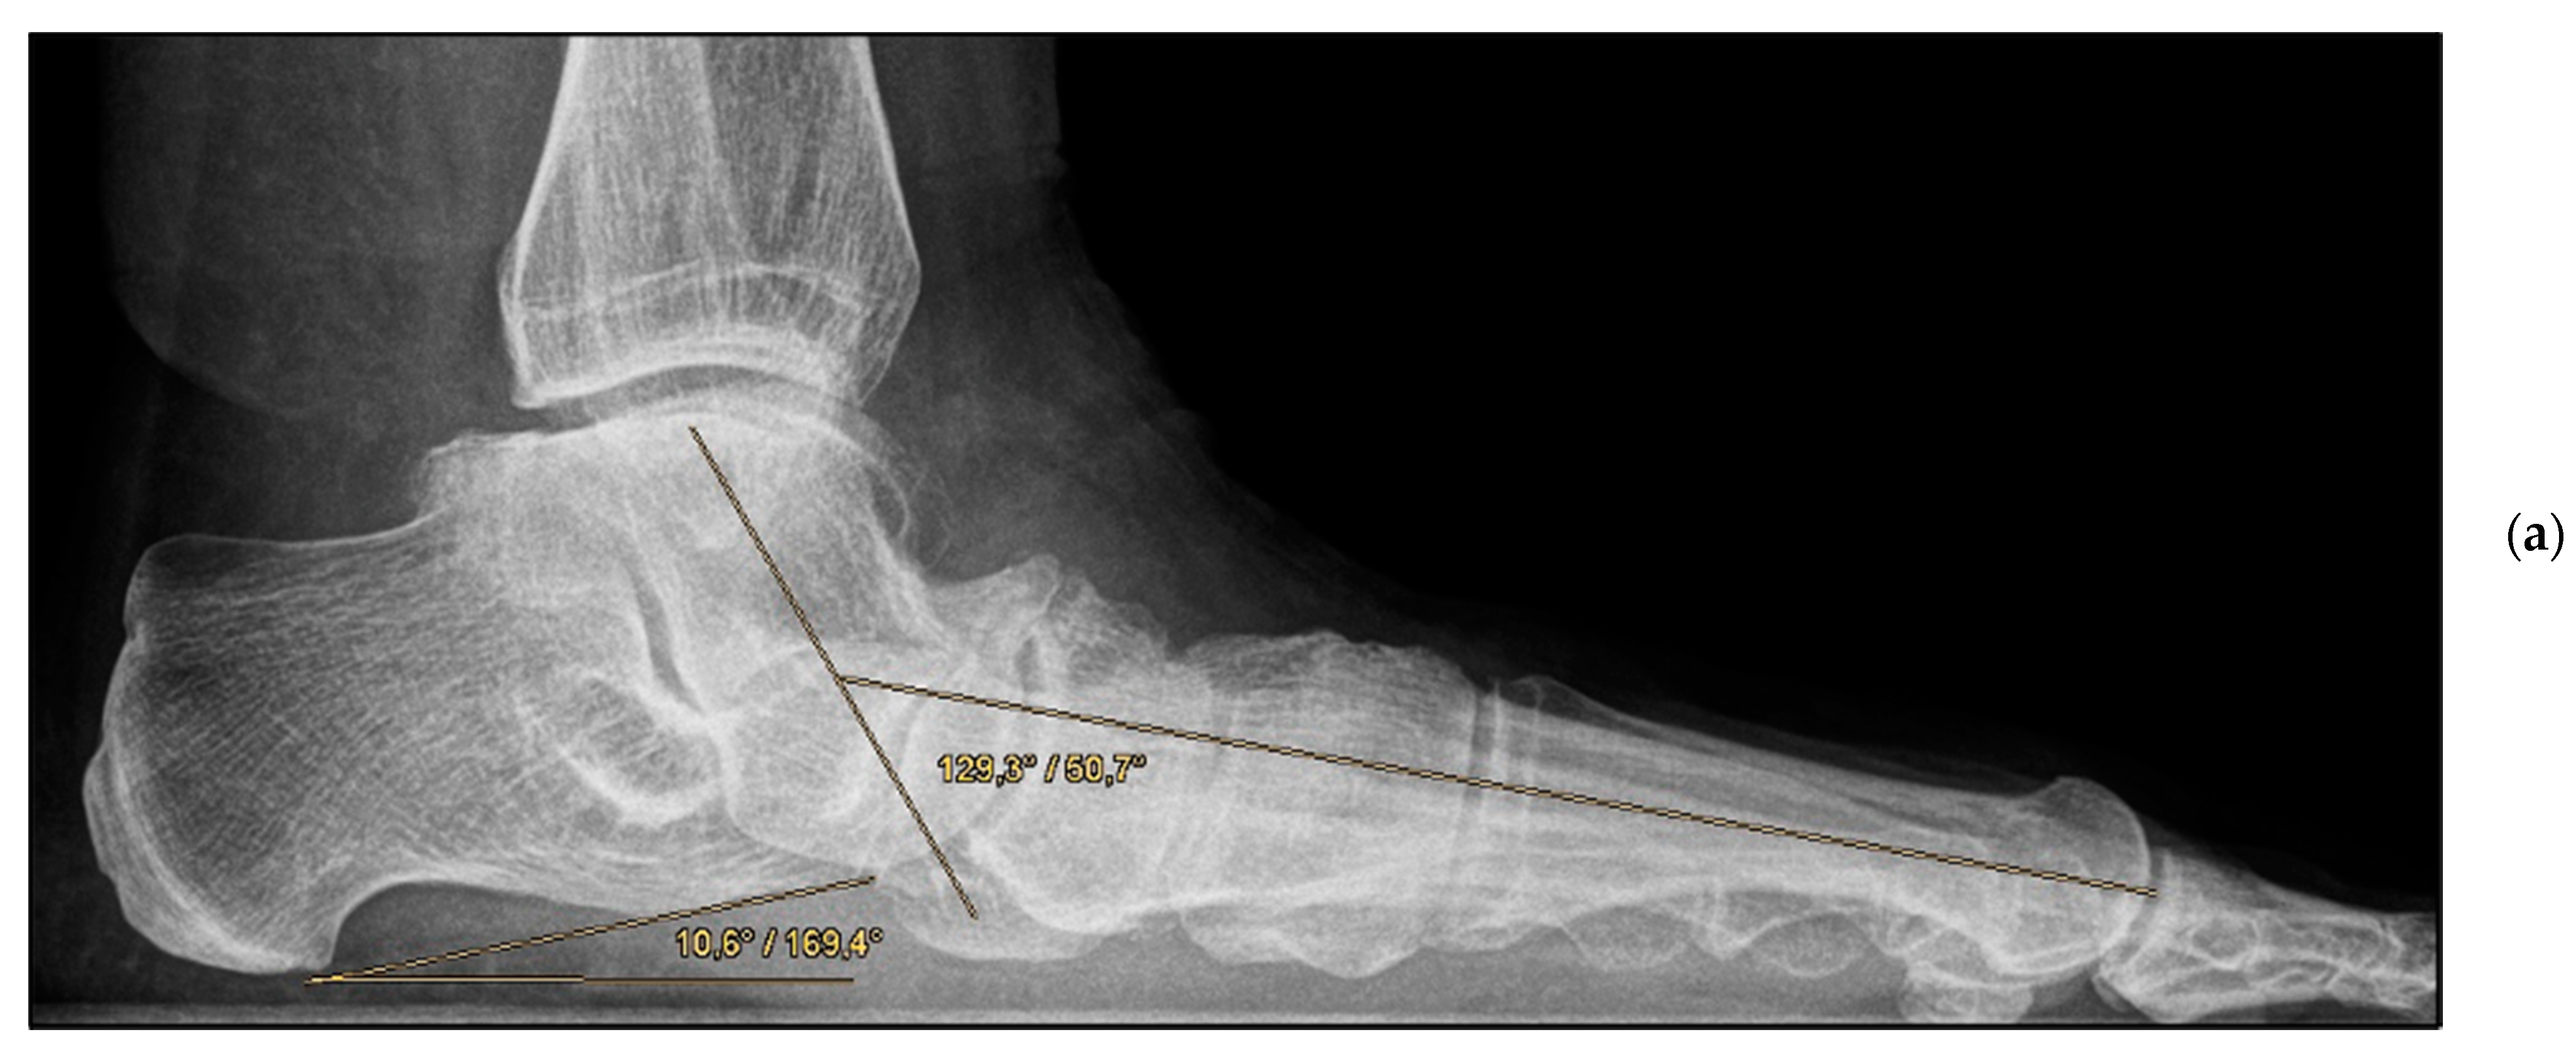

Figure 5.

Pre- and post-operative radiographic findings of double arthrodesis, left foot. (a) Lateral view pre-operative, (b) lateral view post-operative after implant removal.

The mean FFI-D was 33.9 (group A: 34.5; group B: 33.5); the mean SF-12 physical component summary was 43.13 (group A: 40.9; group B: 44.9); and the mean SF-12 mental component summary was 43.13 (group A: 40.9; group B: 44.9) (Table 2). No significant differences were observed between the groups. The post-operative results demonstrated that the angles (talometatarsal and talocalcaneal in the anteroposterior and lateral view) were largely comparable (Table 3). Only the lateral talocalcaneal angle showed a significant difference between the groups (group A: 50.5°; group B: 46.1°; p = 0.047), norm value < 50° [21]. All reconstructed angles were also compared with the clinical scores. No correlation could be found either in the respective group or with all study patients together (e.g., FFI-D versus post-operative dorsal talometatarsal angle, r = 0.023).

Encouragingly, the angles were shown to be comparable to the post-operative values otherwise obtained in joint-preserving procedures in young adults [16]. The talo–first metatarsal angle on lateral view, the so-called Meary’s angle, represents one of the most important radiological criteria regarding the assessment of flatfoot deformity. Thus, in the present study, a moderate-to-severe deformity could be converted into a physiological configuration or at most a mild deformity in all patients, irrespective of the group allocation [31].